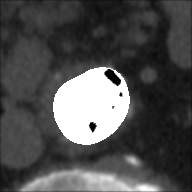

At this point, the dataset is ready for the processing in the portal ImageLab. The latter, takes as input the basal ROI and its corresponding CM one, together with their respective binary masks. These, are used by the algorithm to create the image (see Fig. 2), and consequently to detect the vessel. As depicted in Fig. 4, in output the extracted image is provided, along with a colored map where green highlights pixels correctly classified by the algorithm, red indicates misclassified ones, and white indicates the areas the algorithm should have identified but did not. Adjacent to this, similarity indices described before are presented, computed by considering the CM image as the target, which is provided as input for this purpose. We have processed in the portal each slice of our dataset.

In this version of the algorithm (updated compared to the one described in [30]), the calcium plaques are excluded from the patent lumen of the vessel and therefore visible in the processed image (in black), as we can observe also from Tables 3 and 4. The advantage of removing these structures during the extraction process leads to a more accurate and faithful evaluation of the indices. This observation is illustrated in Figure 6, where we present a comparison of results for a single slice obtained using the previous algorithm version, which does not remove calcium plaques from both the basal and the CM images, and the new algorithm version. The performance improvement is evident, particularly in the DCI index, where a difference is observed: of white pixels are accurately classified with the old version, compared to with the new version. Finally we highlight how, in the new version of the algorithm, the removal of the calcium plaques from both the basal and the CM images produces a different extraction of the patent lumen of the vessel, which in addition to being compatible with the algorithm’s steps, also turns out to be more accurate.

DCI: 0.894 | ||

| : -0.075 |